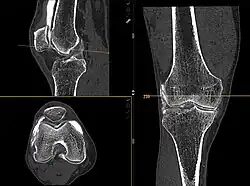

Computertomografie eines Knies, aufgenommen mit einem photonenzählenden CT. Schichtdicke ist 0,6 mm, mittleres CTDIvol ist 9,24 mGy

Bei einem quantenzählenden bzw. photonenzählenden Detektor entfällt der Umwandlungsschritt. Röntgenphotonen werden in den Halbleiterdetektoren direkt in einen elektrischen Strom umgewandelt, so dass die Information über ihren Energiegehalt erhalten bleibt. Als Detektormaterial können Cadmiumtellurid, Cadmiumzinktellurid oder Silicium benutzt werden. Korrekt implementiert bietet der Ansatz des Photon Counting CT (PCCT) den Vorteil einer mehr als doppelt so hohen räumliche Auflösung[35] sowie eine niedrigere Röntgendosis im Vergleich zu konventionellen Geräten. Auch können adipöse Patienten mit besserer Bildqualität untersucht werden. Durch einen geeigneten Schwellwert für die Energie der Photonen kann elektronisches Rauschen weitgehend herausgefiltert werden, was sich vor allem bei Untersuchungen mit niedriger Strahlendosis bemerkbar macht. Durch die Möglichkeit, die Energie der einzelnen Photonen zu kennen, ist eine Multispektral-Untersuchung ohne zusätzlichen Aufwand möglich.[36][37]